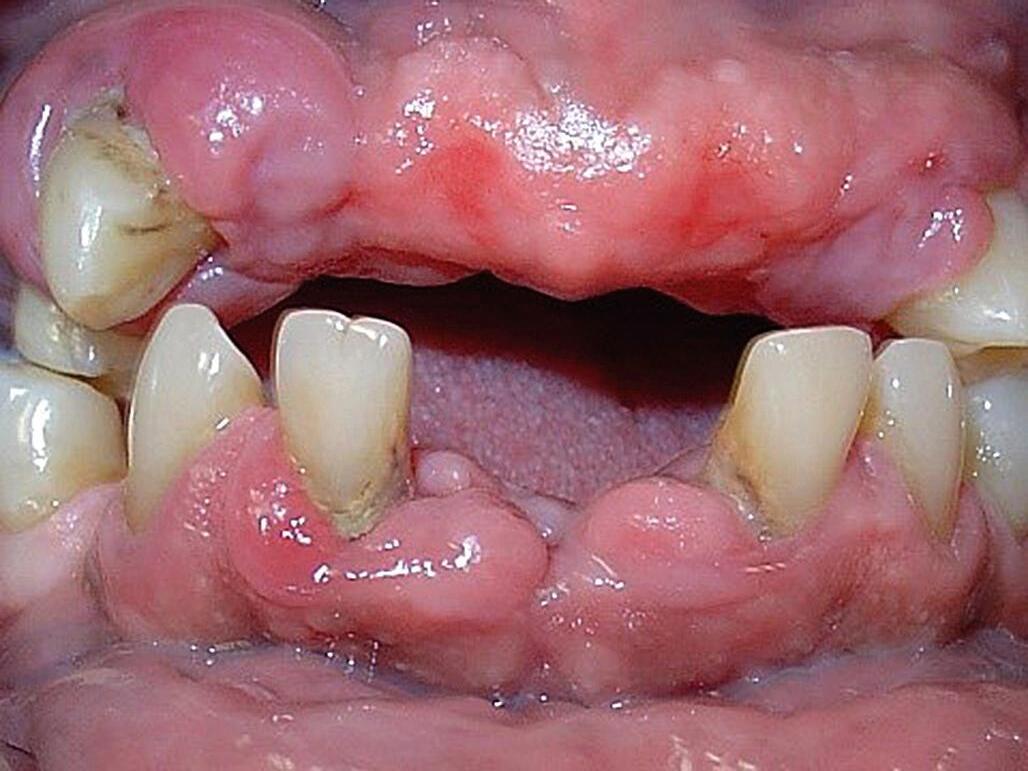

Fig. 20-2. Paciente de 78 anos, gênero masculino, com quadro de hipertensão arterial, fazendo uso de anlodipino – fármaco que influencia na saúde do tecido gengival, principalmente quando o controle de biofilme é ineficiente.

Fig. 20-3. Paciente de 78 anos, gênero masculino, portador de demência, com raízes expostas em decorrência de escovação com força demasiada.